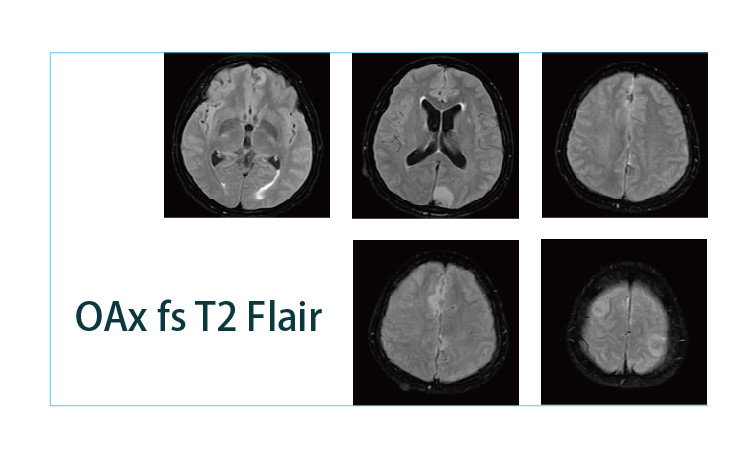

【朗润影像档案】磁共振影像病例分享(编号20190412)

2019-04-25 17:22:57